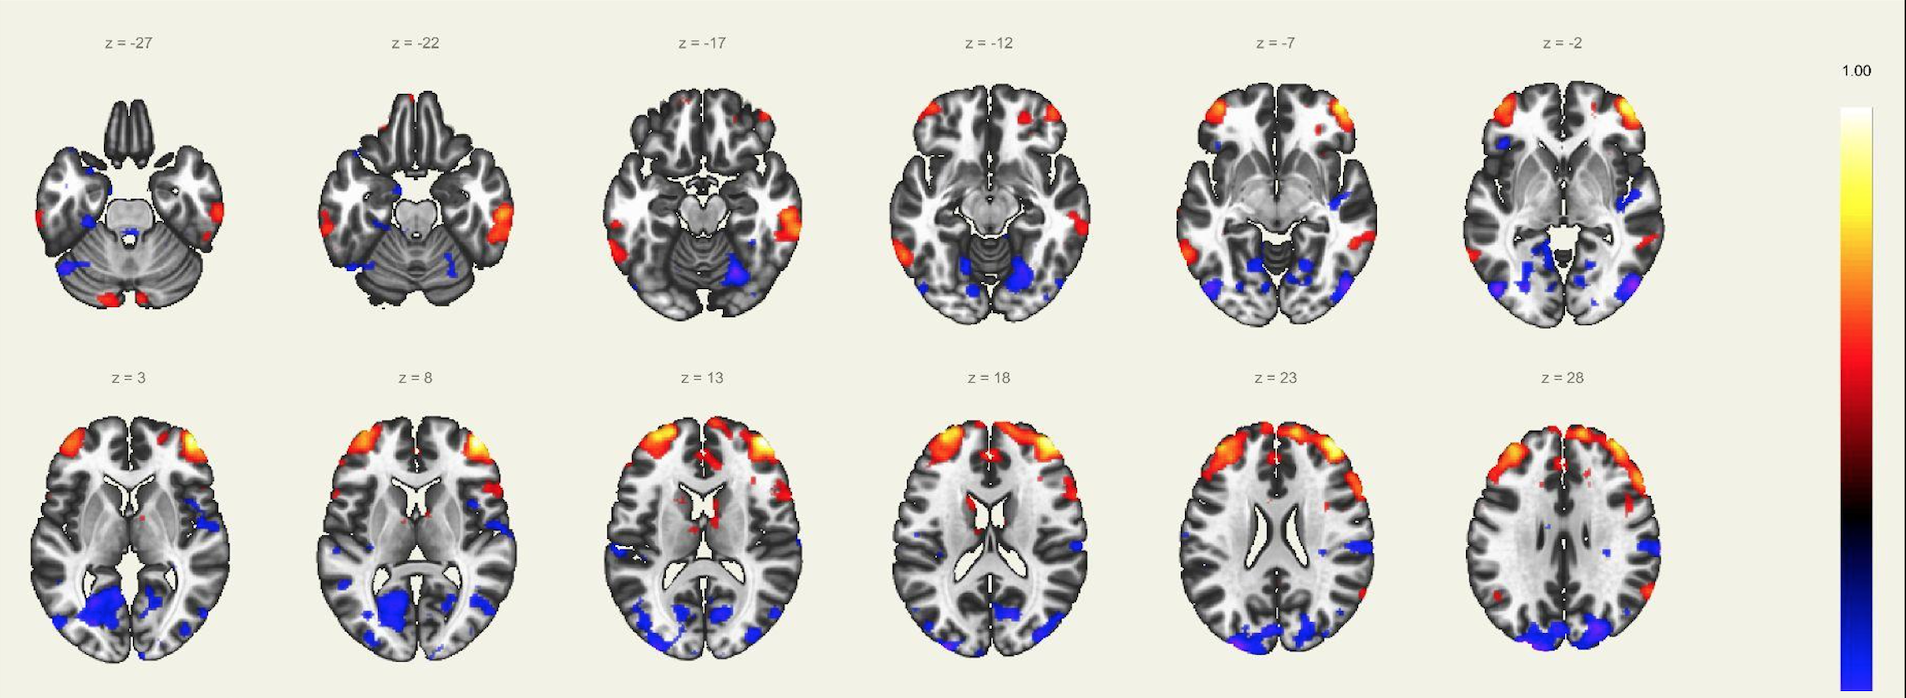

En este estudio, el escaneo se realizó con un resonador de 3 Tesla del servicio de diagnóstico por imágenes de la Clínica Internacional, a un paciente joven, sin comorbilidades ni antecedentes de importancia, el cual estuvo despierto en todo momento y con los ojos cerrados. Además, se le dio instrucciones de completar palabras mentalmente sin emitir sonido alguno o hacer gestos, llegando a identificarse las distintas redes cerebrales detalladas posteriormente.

El estudio fue realizado con secuencia BOLD, con los siguientes parámetros: cortes: 40, factor de distancia: 0%, Field of View: 240 mm, grosor de corte: 4 mm, tamaño de vóxel: 3.8 x 3.8 x 4 mm, TR: 3000 ms, TE: 30 ms, Umbral: 4 y tamaño del paradigma 20.

A pesar de la ausencia actividad física, resulta imposible indicar que no se esté realizando ningún tipo de actividad mental, como recuerdos o el uso de la imaginación. La consecuencia de esto se ve reflejada en los cambios de la actividad neuronal.16 A través de este método de vóxel semilla se ha logrado identificar distintas redes de conectividad funcional descritos a continuación:

Red de Atención Dorsal:

Constituida por la corteza cingular anterior, ambas ínsulas y el área motora suplementaria, la cual juega un rol importante en la regulación de los cambios dinámicos en las otras redes, por lo que su disfunción afecta directamente en el correcto funcionamiento de las otras redes. Otra característica conocida, es la necesidad de operatividad de esta área para la realización de rápidos cambios de comportamiento. Evidentemente, el inicio del control de los procesos de cognición se ve determinado por el correcto funcionamiento de esta red sobresaliente.

Red Visual:

Se ha reportado la activación sincrónica en los surcos calcáreos, regiones extraestriadas, área inferior de la precuña y el núcleo geniculado lateral del tálamo, el cual se conecta funcionalmente con la corteza visual primaria en el lóbulo occipital. Estos a su vez se organizan en áreas visual medial (región extraestriada, división inferior de la precuña y núcleo geniculado lateral) y lateral (unión occipito temporal abarcando el polo occipital y la región parietal superior).

Red Visuo-Espacial:

Asociada a la red visual, compuesto por la corteza parietal posterior de la unión occipito parietal, región media de la precuña, corteza cingular posterior y el polo frontal, por lo que la afección de estas regiones puede afectar la atención espacial del individuo. Por lo que se infiere que la corteza parietal posterior está involucrada en orientarse hacia señales visuoespaciales sobresalientes.

Red del Lenguaje:

Implica las regiones prefrontales, temporo-parietal y subcortical, además de las ya conocidas áreas de Broca y Wernicke. El habla, el entendimiento, lectura, interpretación, mímicas; son algunas de las funciones más importantes de esta red. Adicionalmente, el área de Broca es asiento de las neuronas espejo, las cuales intervienen en el entendimiento e imitación de actividades motoras.